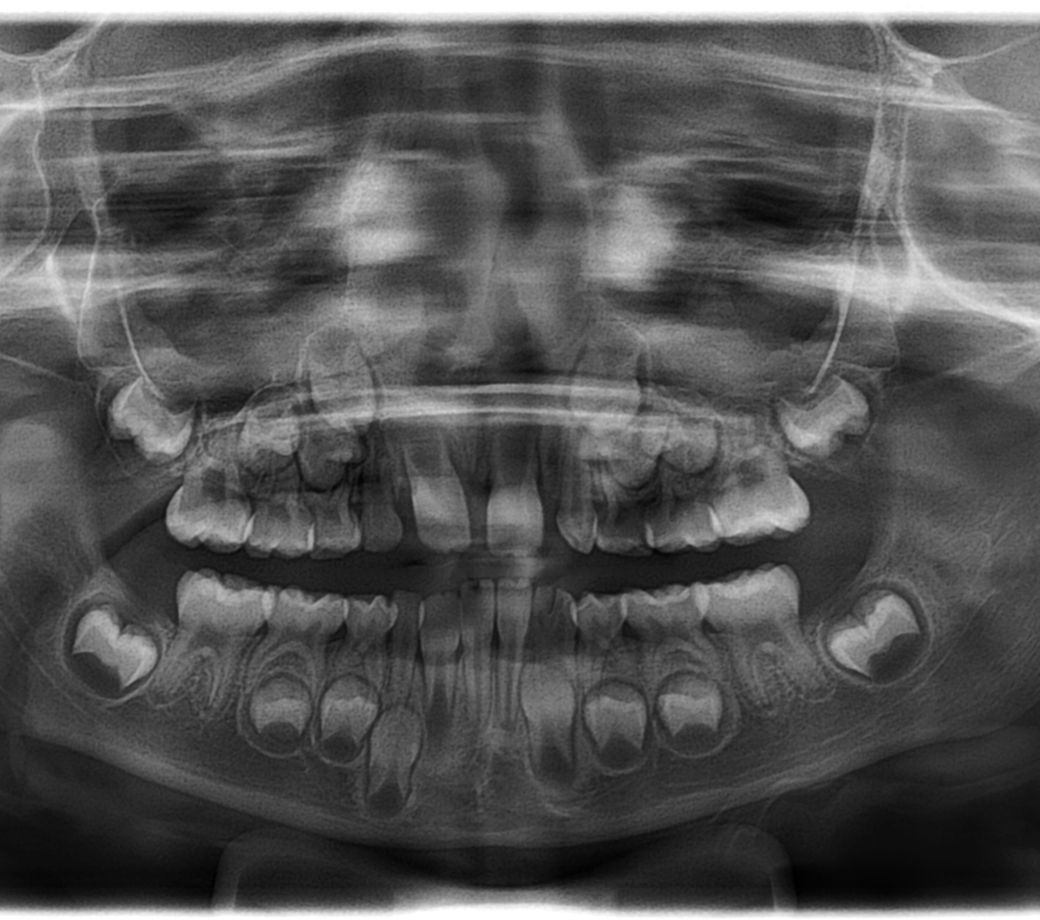

아이가 상악 앞니 측절치 2개

하악 앞니 측절치 1개 결손 입니다

영구치가 다 나면 교정을 할 예정이었는데

영구치 결손인 아이라서 어차피 다시 교정을 할 것이니

( 영구치 결손 이지만 얼굴뼈가 작아서 자리가 남지는 않아요 그래서 인플란트 필요 없다고 진단 받았어요)

교정 전 찍었던 파노라마도 첨부합니다

아직 영구치가 맹출된 상태가 아니라 치아들이 나올 공간만 확보한거 같습니다. 추후에 영구치가 다 맹출되고 나서 다시 확인을 할것같습니다.